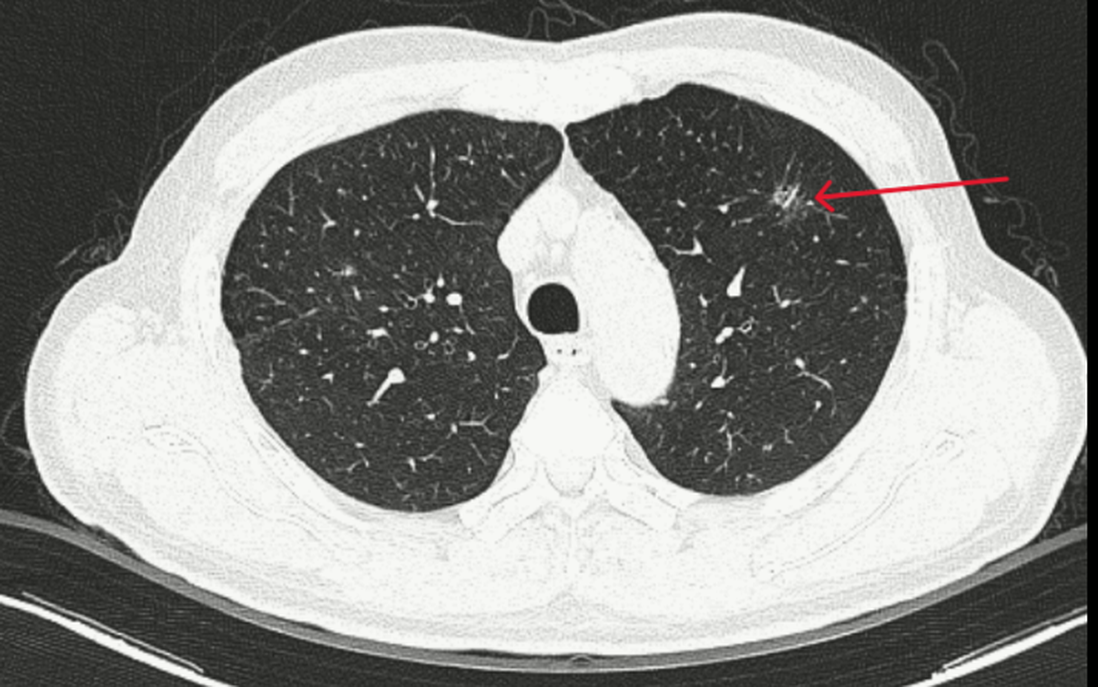

Tuy nhiên, điều đáng chú ý xảy ra khi bác sĩ tiến hành chụp CT để đánh giá tổn thương thận: hình ảnh thu được cho thấy một nốt kính mờ dạng tua gai ở thùy trên phổi trái - dấu hiệu gợi ý tổn thương ác tính.

Các xét nghiệm máu, sinh hóa và đông máu đều trong giới hạn bình thường. Marker Cyfra 21-1 tăng nhẹ - một trong những chỉ dấu liên quan đến ung thư phổi. Trong khi đó, CT ngực ghi nhận tổn thương kính mờ bờ tua gai, còn CT bụng phát hiện giãn đài bể thận và sỏi niệu quản.

Hình ảnh vài đám tổn thương dạng kính mờ bờ tua gai ở thùy trên phổi trái